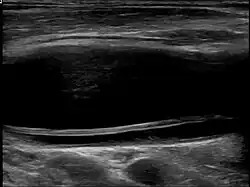

Carotid artery dissection can occur spontaneously or be triggered by trauma, including minor injuries, certain medical conditions, or activities that involve neck movement. It is a leading cause of stroke in young and middle-aged adults. The condition is typically diagnosed through imaging studies, such as ultrasound, magnetic resonance imaging (MRI), magnetic resonance angiography (MRA), or computed tomography angiography (CTA), which help visualize the blood vessels and detect abnormalities.

| Diagnostic method | Ultrasound, MRI, MRA, CTA |